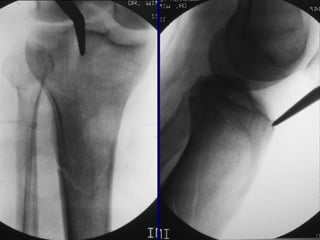

Reduction

• Proximal Fractrues are technically more

challenging

• Prone to Valgus &

• Pro-curvatum deformities

Technique

• Screws placed on

concave side of

deformity.

Blocking (Poller) Screws

• Functionally narrow im canal

• Increase strength and rigidity of fixation

The Use of Poller Screws as Blocking

Screws in Stabilising Tibial Fractures

Treated with Small Diameter Nails

• 21 patients

• All healed within 3-12 months

• Mean alignment 1 degree valgus, antecurvatum 2

degrees.

Krettek C, et al. JBJS 81B: 963, 1999

• Entry Site for Proximal

fractures Critical

• Reference is

Lateral Tibial Spine